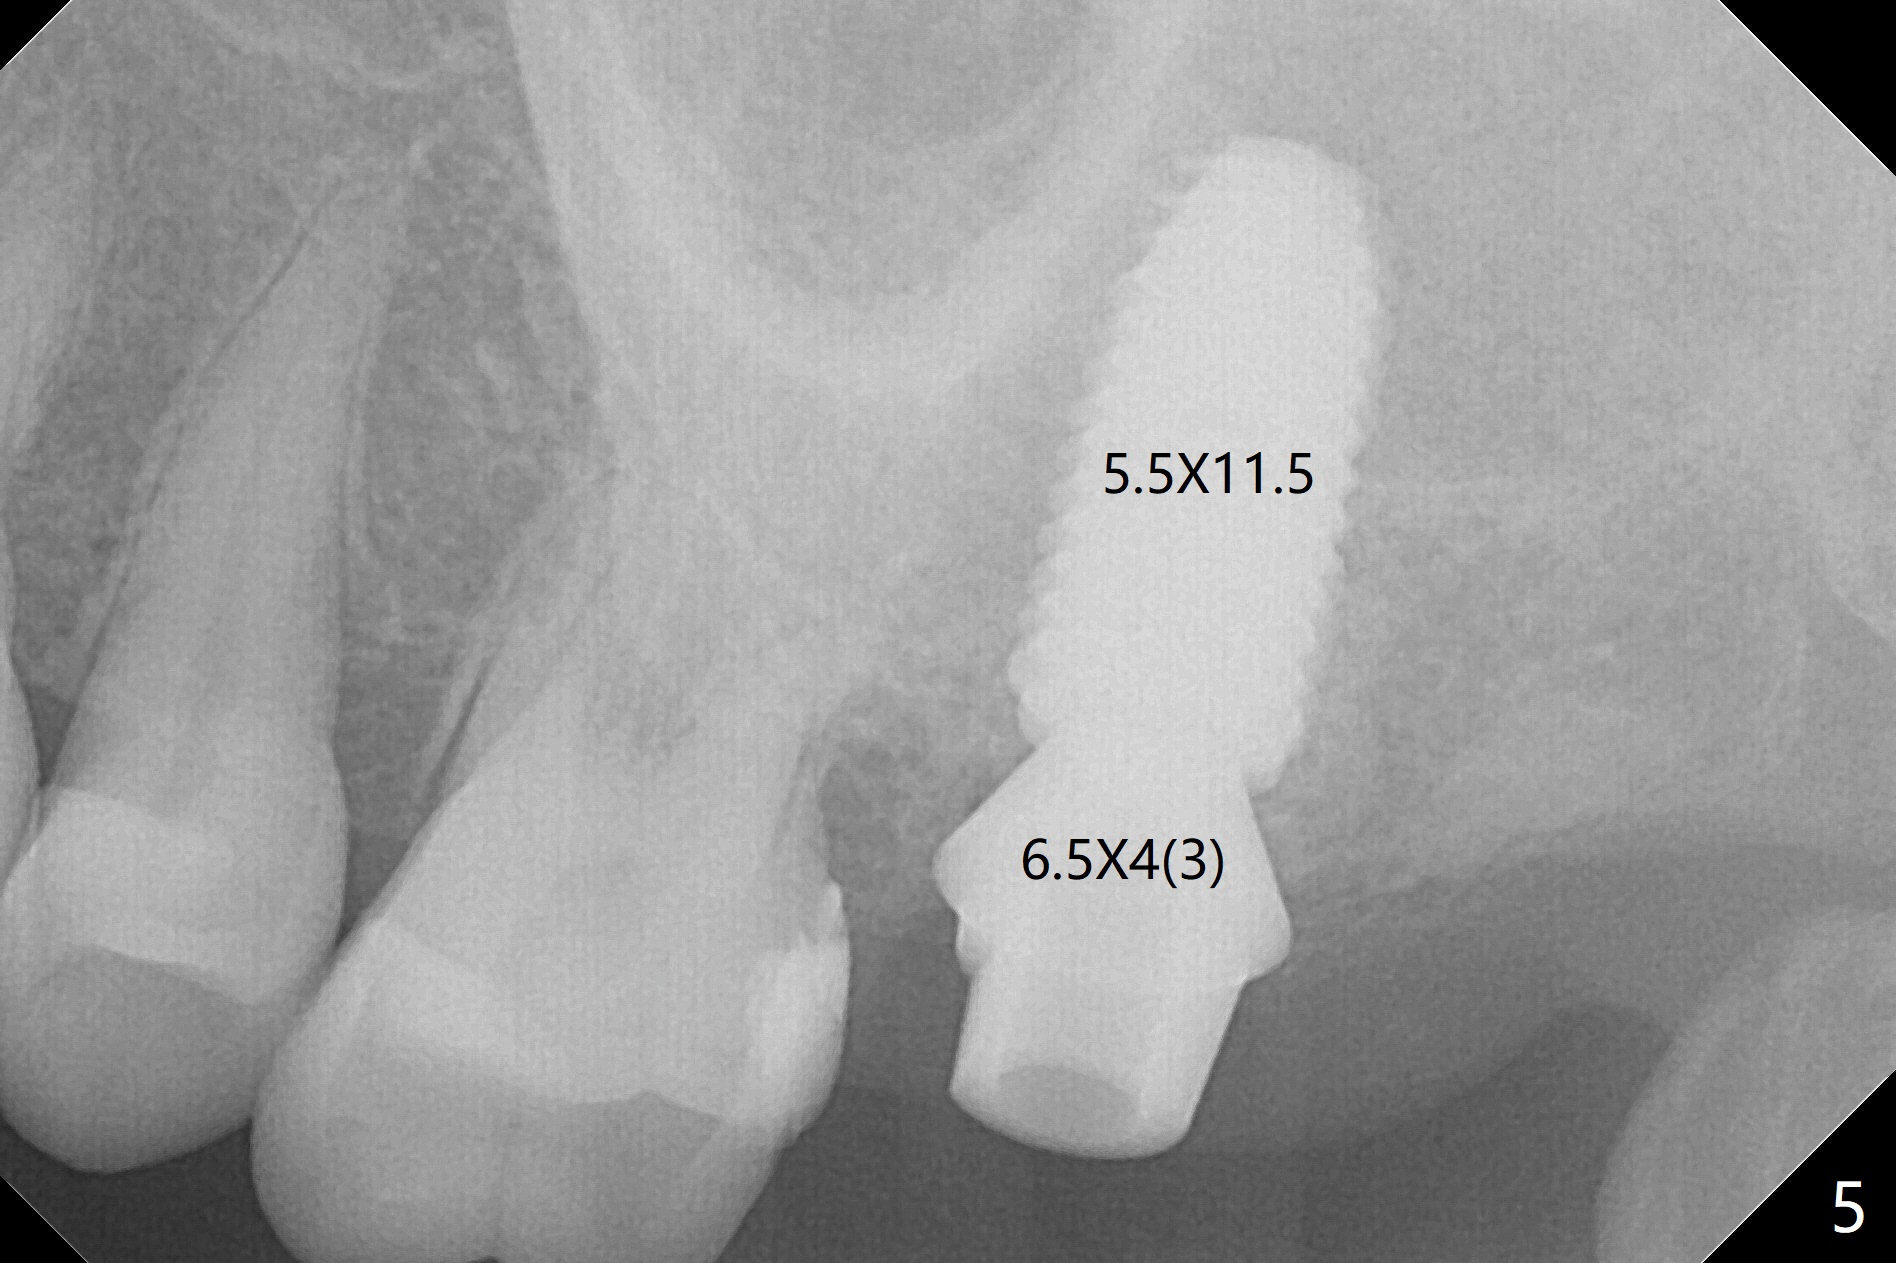

While the tooth #2 has a mesiodistal crack line with symptom (Fig.1 arrowheads, crown pending), the tooth #15 has a mesiodistal fracture (Fig.2). Immediately preop 5x5 cm CBCT (Fig.3) confirms the palatal (P) fracture with palatal bone loss. Although a 5x7.3 mm implant fits the site by design (Fig.4), a much longer implant is required to achieve primary stability past the sinus floor using IBS Magic Expanders (Fig.5,6 (20-30 Ncm; sinus lift with PRF membrane and allograft)). In contrast, primary stability could not be obtained by engaging dummy implant to the socket walls. A short implant without sinus lift is associated with less obvious complication such as fibrointegration. The implant seems osteointegrated 4.5 months postop (Fig.7). The abutment is changed to 6.5x4(5) mm before impression. There is no bone loss 5 months post cementation (Fig.8 (11 months postop)). It is the same 2.5 years post cementation (Fig.9,10).